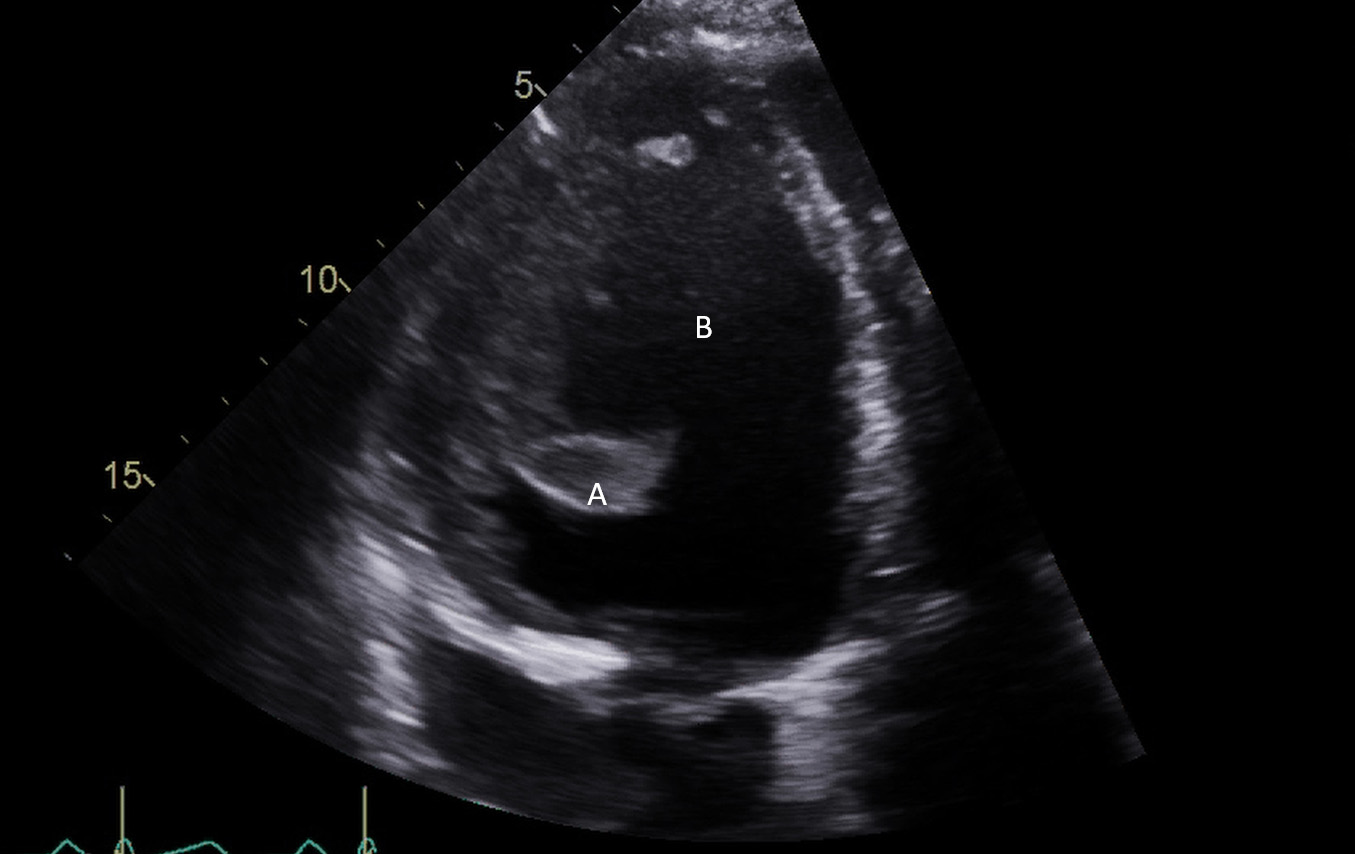

Fig. 6.A midesophageal long axis view zoomed up on the aortic valve demonstrating the Impella traversing an open aortic valve. (A) Impella. (B) Ascending aortic root.

Fig. 7.A parasternal long axis view on a transthoracic echocardiogram. The distance from the Impella inlet to the aortic valve is measured and noted to be 3.9 cm. (A) LV Cavity. (B) Impella. (C) Ascending aortic root.